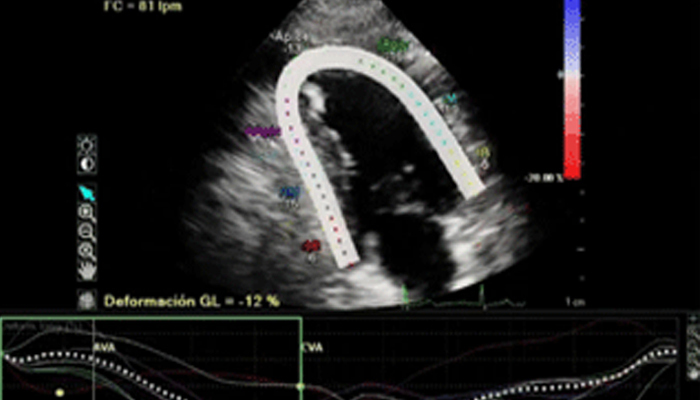

تشهد حاليًا خيارات العلاج التي لا تتطلب سوى تدخل جراحي محدود في القلب والأوعية الدموية انتشارًا ملحوظًا. ولقد ساهمت التطورات الأخيرة في مجالات التشخيص والتوجيه بالصور المباشرة Live Image Guidance والمعلوماتية في جعل هذا الأمر ممكنًا. بالتعاون مع أشهر أطباء أمراض القلب، ابتكرنا حلولاً تساهم في منح المرضى الفرصة لتغيير حياتهم. فهذه الحلول تساعد في تسريع سير العمل وزيادة فعالية الطاقم الطبي وتوفير أفكار سريرية.

تعلّم كيف تستطيع الحلول التي ابتكرناها في مجال طب القلب مساعدة مؤسستك